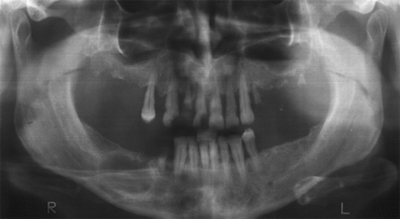

In addition, one example of a lower jaw, though the clinic is full of similar ones. Both the X-ray and the diagram show that there are no cysts, but the dentist diagnosed them and referred the patient for surgery. Black arrows indicate one large cyst and white arrows indicate one small and one large cyst. In fact, what the colleague considered a large cyst is a malformation of the mandibular canal, in which the lower part limited by the compact, and the upper, adjacent to the apexes of the roots, which appear to be “immersed” in the “cyst”, which in turn proceeds from them. , is simply a variation on the anatomy of the canal. The dark spot that indicates the back white arrow is the mental aperture, and that indicated by the front white arrow is an artifact due to the X-ray orthopantomography technique.